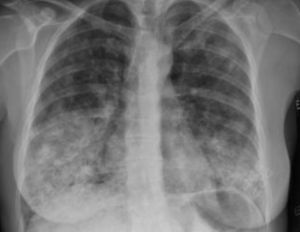

Tras la estabilización hemodinámica de las primeras horas del ingreso en observación, la paciente presentó deterioro respiratorio intenso y progresivo requiriendo soporte ventilatorio mediante ventilación mecánica no invasiva tipo BIPAP. Por la situación clínica de gravedad de la paciente y los hallazgos analíticos y radiológicos obtenidos hasta ese momento, sin un claro juicio clínico definido, se comentó el caso con la unidad de cuidados intensivos y se procedió al ingreso a su cargo donde presentó mejoría progresiva respiratoria en los días posteriores y donde se mantuvieron unas saturaciones de oxígeno del 95% con gafas nasales, sin sensación de disnea añadida. Al no presentar signos de infección durante el ingreso se suspendieron los antibióticos al séptimo día. La radiografía torácica simple fue mejorando progresivamente, en posible relación con la administración de corticoides hasta presentar una imagen al alta casi sin alteraciones (fig. 2).

Radiológicamente, pueden hallarse infiltrados bilaterales múltiples con nódulos que se localizan frecuentemente en los lóbulos inferiores y medios, y que miden entre 1 y 5cm de diámetro. Pueden cavitarse o tener patrones migratorios. Por lo regular, duran de 8 a 12 semanas, aunque se han informado casos más persistentes. Puede haber derrames pleurales, infiltrados alveolares difusos a consecuencia de una hemorragia alveolar, linfadenopatías hiliares y mediastínicas y daño intersticial. La TC de tórax define mejor estos hallazgos radiológicos. En el 10% de los casos puede desarrollarse una hemorragia pulmonar masiva por capilaritis alveolar, siendo esta la primera causa de hemorragia alveolar difusa, situación presente en nuestra paciente. La TC de tórax define mejor estos hallazgos radiológicos1.